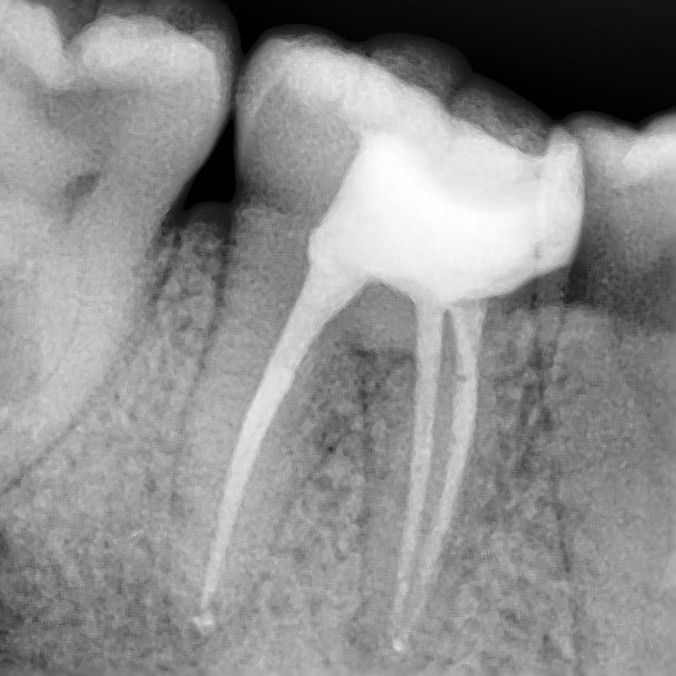

We pay great attention to the procedure of root canal treatment, so we have established the detailed protocol of root canal treatment which provides thorough removal of all the organic elements which may cause inflammation and in six months after completion of treatment we also provide repeated X-rays examination to control hermicity of canal filling and absence of reinfection.

precise determination of the shape of the channels

High-precision X-ray shows the shape of the canals and the area of inflammation

control x-ray